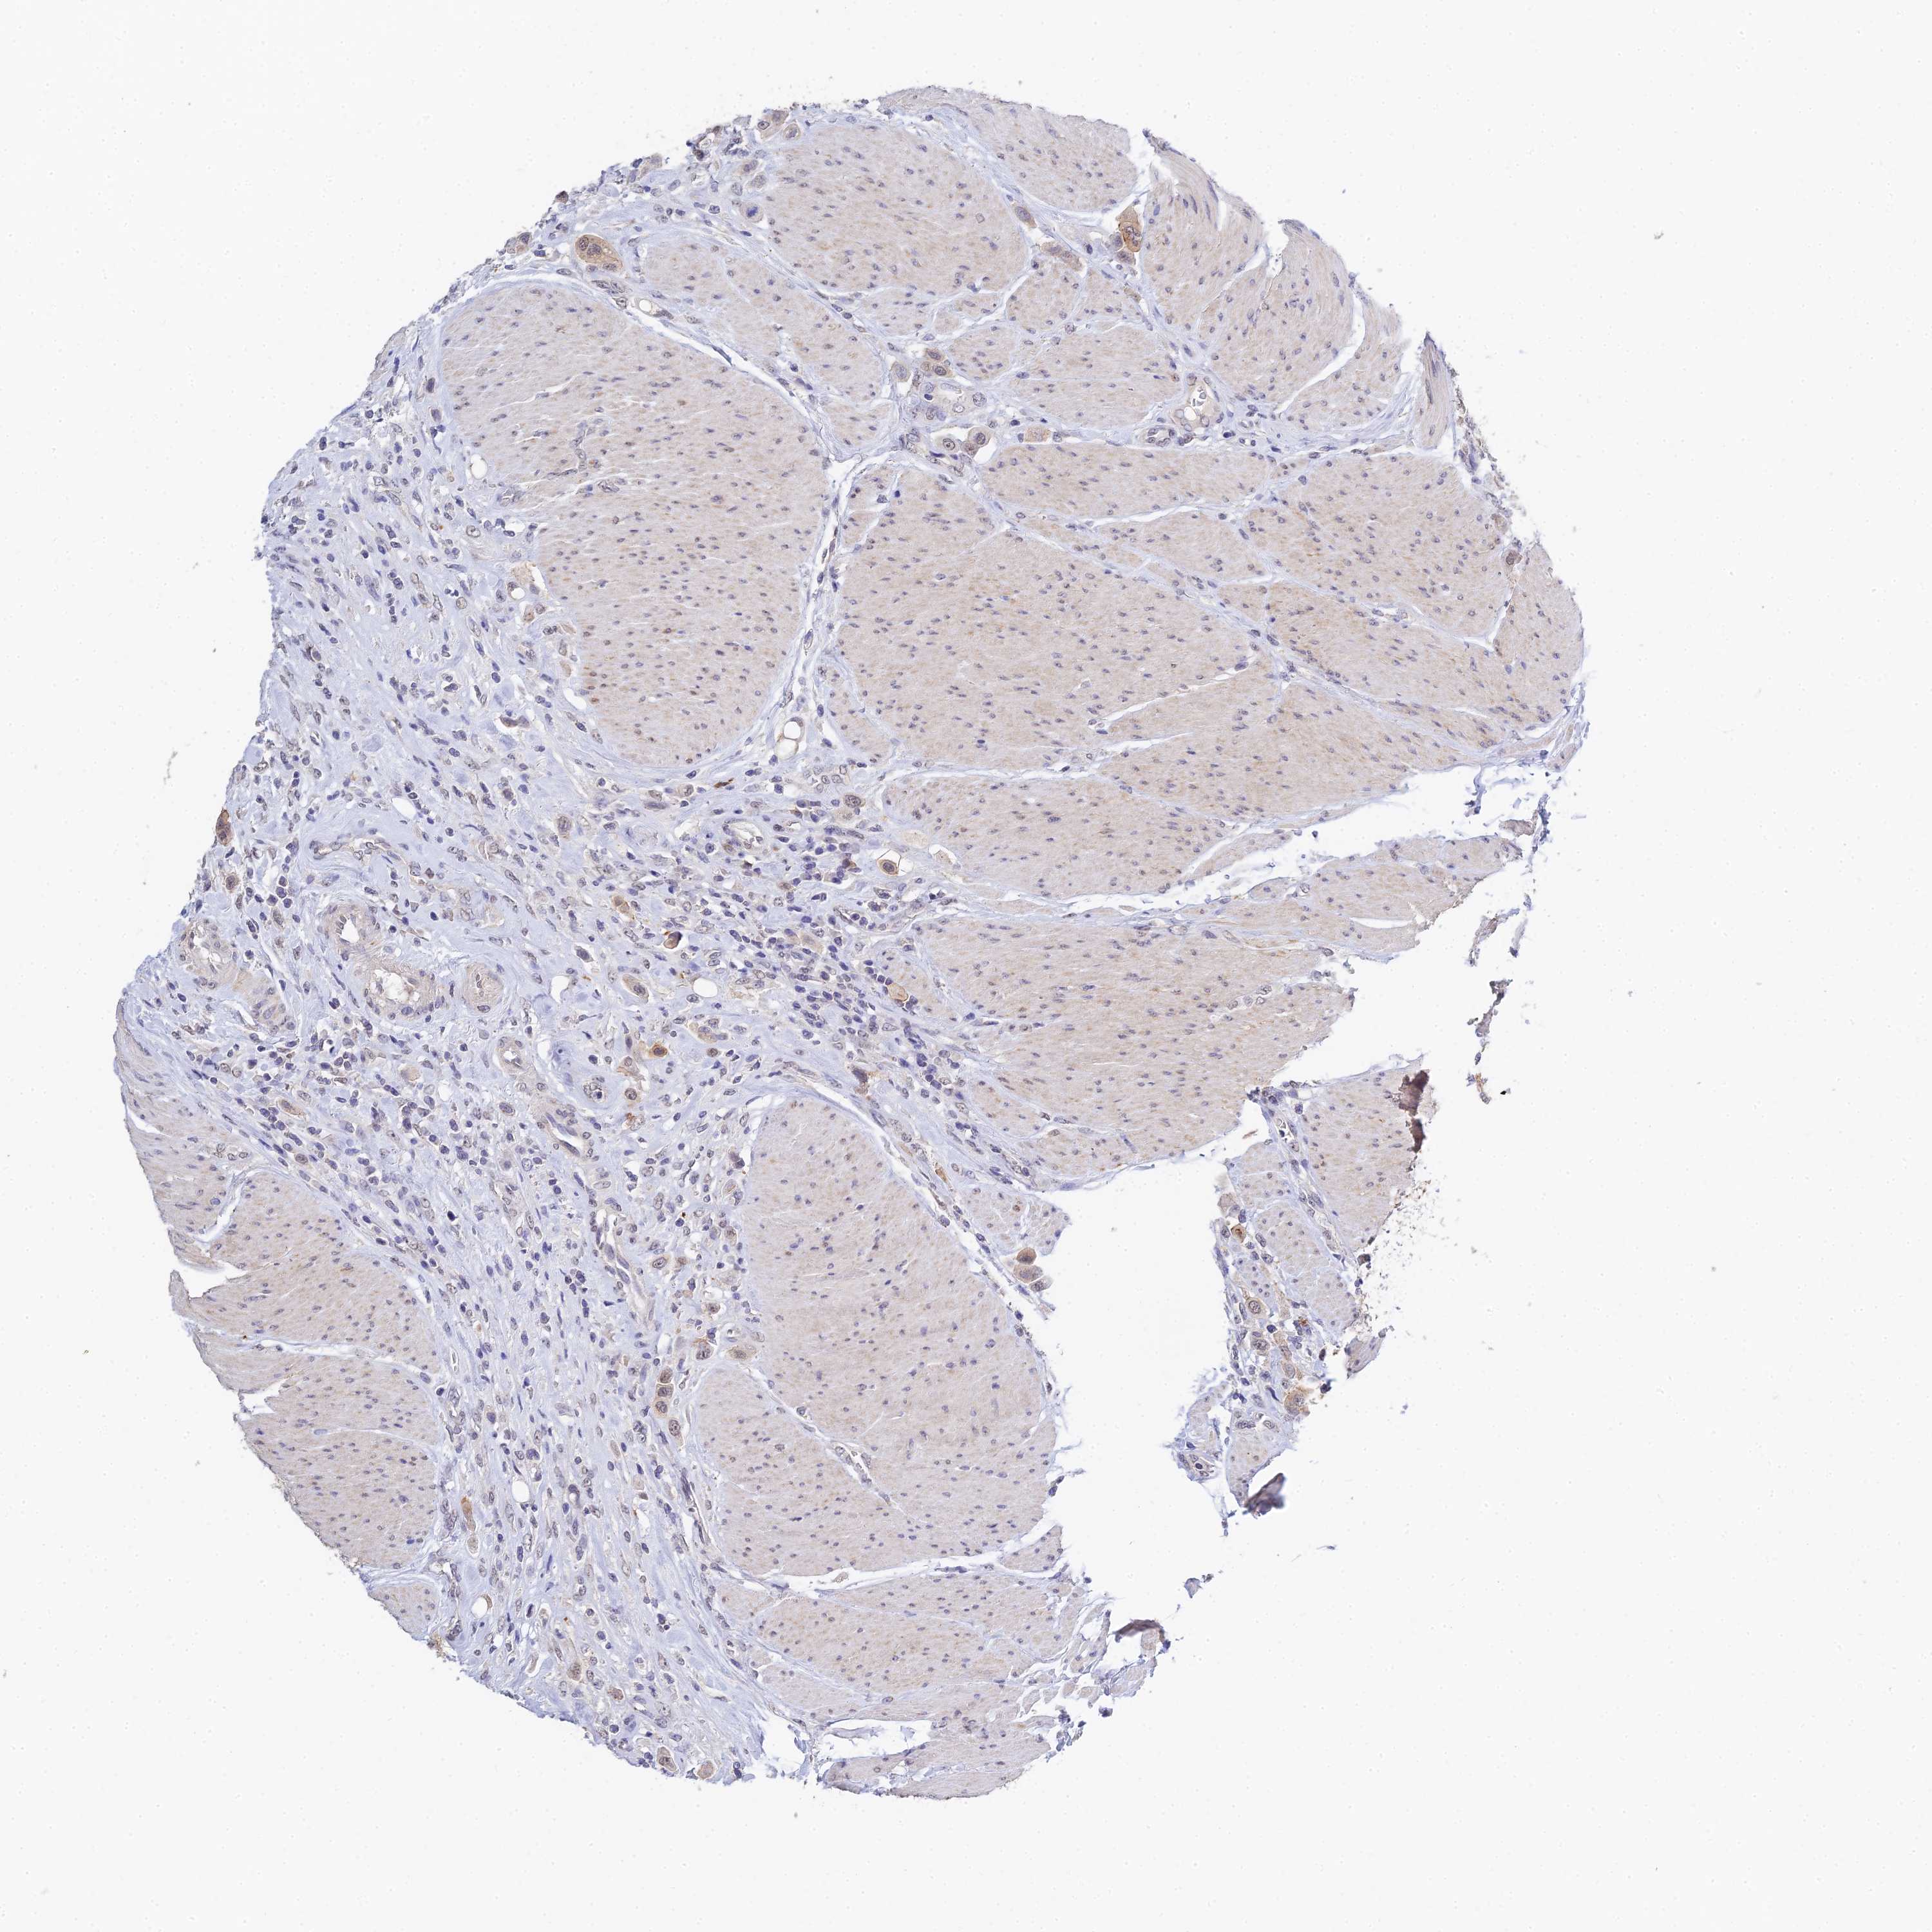

UROTHELIAL CANCER - Protein expressioni

A mouse-over function shows sample information and annotation data. Click on an image to view it in a full screen mode. Samples can be filtered based on level of antibody staining by selecting one or several of the following categories: high, medium, low and not detected. The assay and annotation is described here.

Antibody stainingi

Antibody staining in the annotated cell types in the current human tissue is reported as not detected, low, medium, or high, based on conventional immunohistochemistry profiling in selected tissues. This score is based on the combination of the staining intensity and fraction of stained cells.

Each image is clickable and will lead to virtual microscopy that enables deeper exploration of all samples and also displays staining intensity scores, fraction scores and subcellular localization as well as patient and tissue information for each sample.

Antibody HPA044576

Staining

High

Medium

Low

Not detected

Intensity

Strong

Moderate

Weak

Negative

Quantity

>75%

75%-25%

<25%

None

Location

Nuclear

Cytoplasmic/membranous

Cytoplasmic/membranous,nuclear

Urothelial carcinoma, High grade

Urothelial carcinoma, Low grade

Urothelial carcinoma, NOS